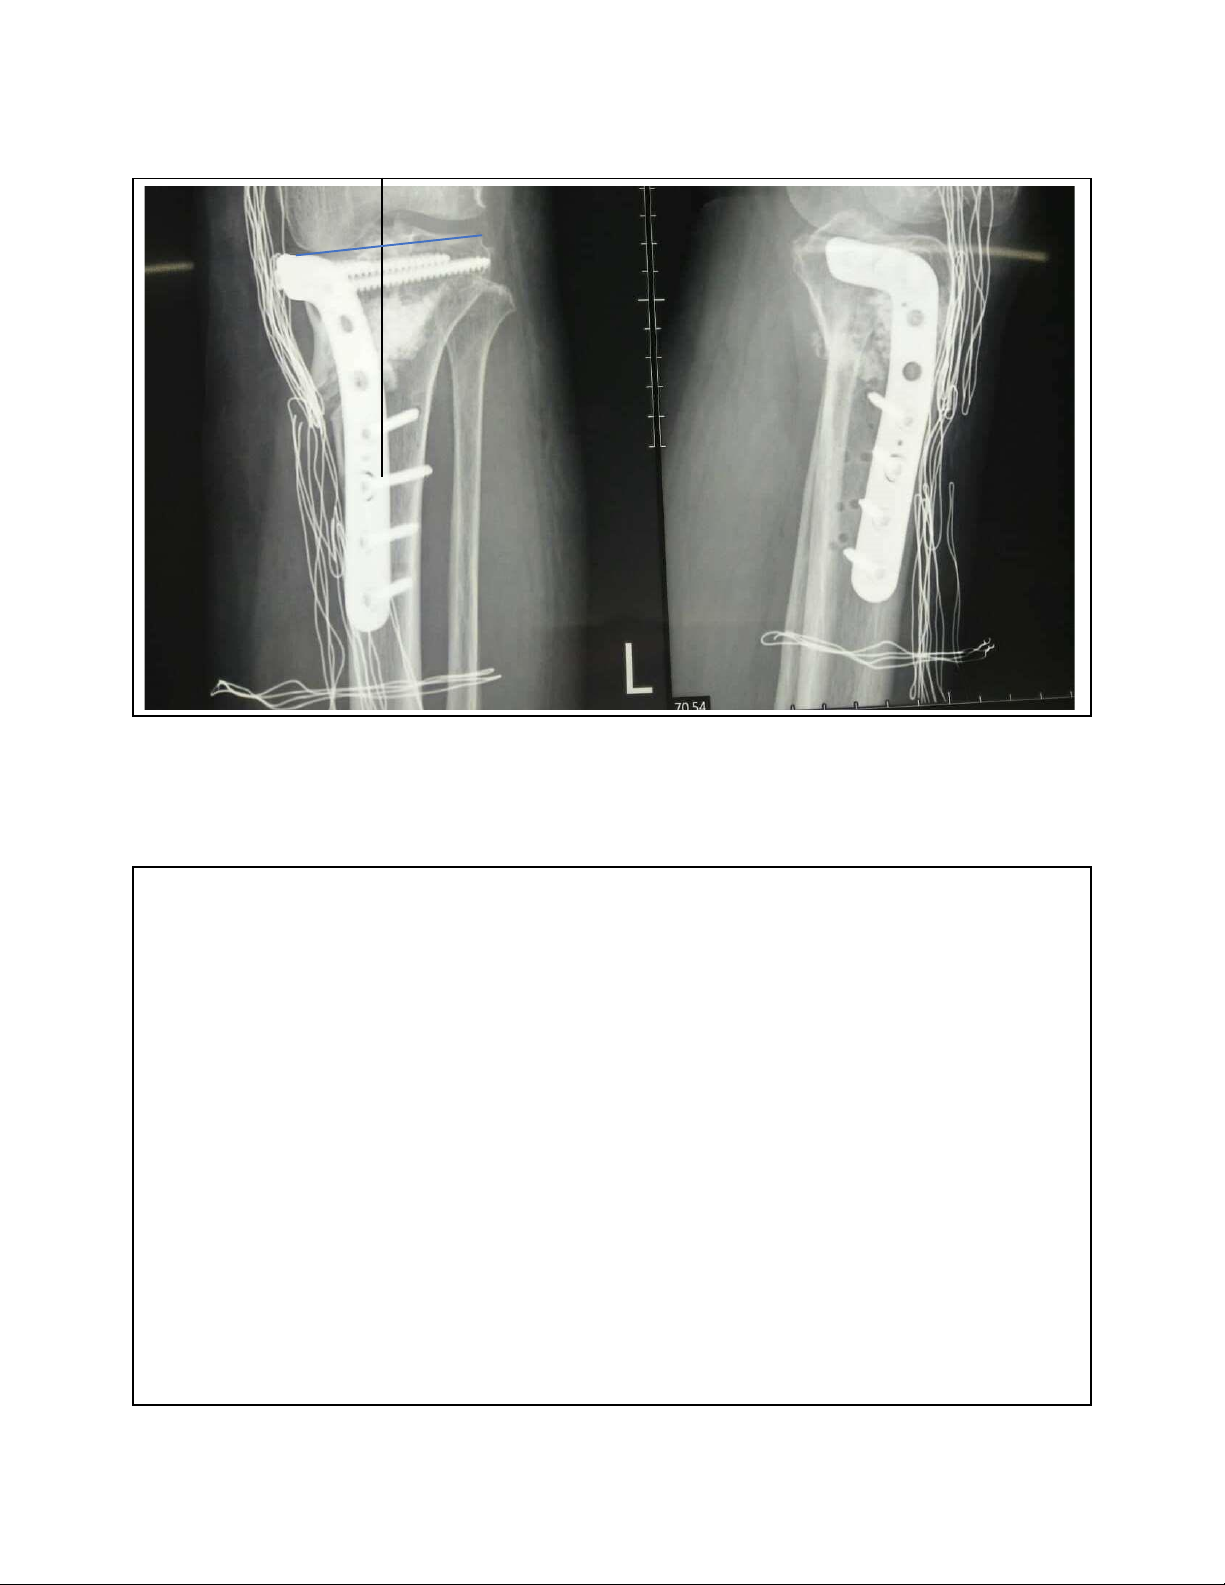

Vẹo trong(varus) trước và sau cắt xương 30 lOMoAR cPSD| 22014077 7/15/2023 Bn nữ 58t, gãy mâm chày 14th • Thay khớp hay bảo tồn khớp? 31 Chân vẹo trong sau mổ KHX 32 lOMoAR cPSD| 22014077 7/15/2023 33 lOMoAR cPSD| 22014077 7/15/2023 1 năm sau mổ 34 Dáng

i bình thường, trục thẳng và không au 35 lOMoAR cPSD| 22014077 7/15/2023 Thay khớp •Thay khớp 1 phần •Thay toàn phần 36